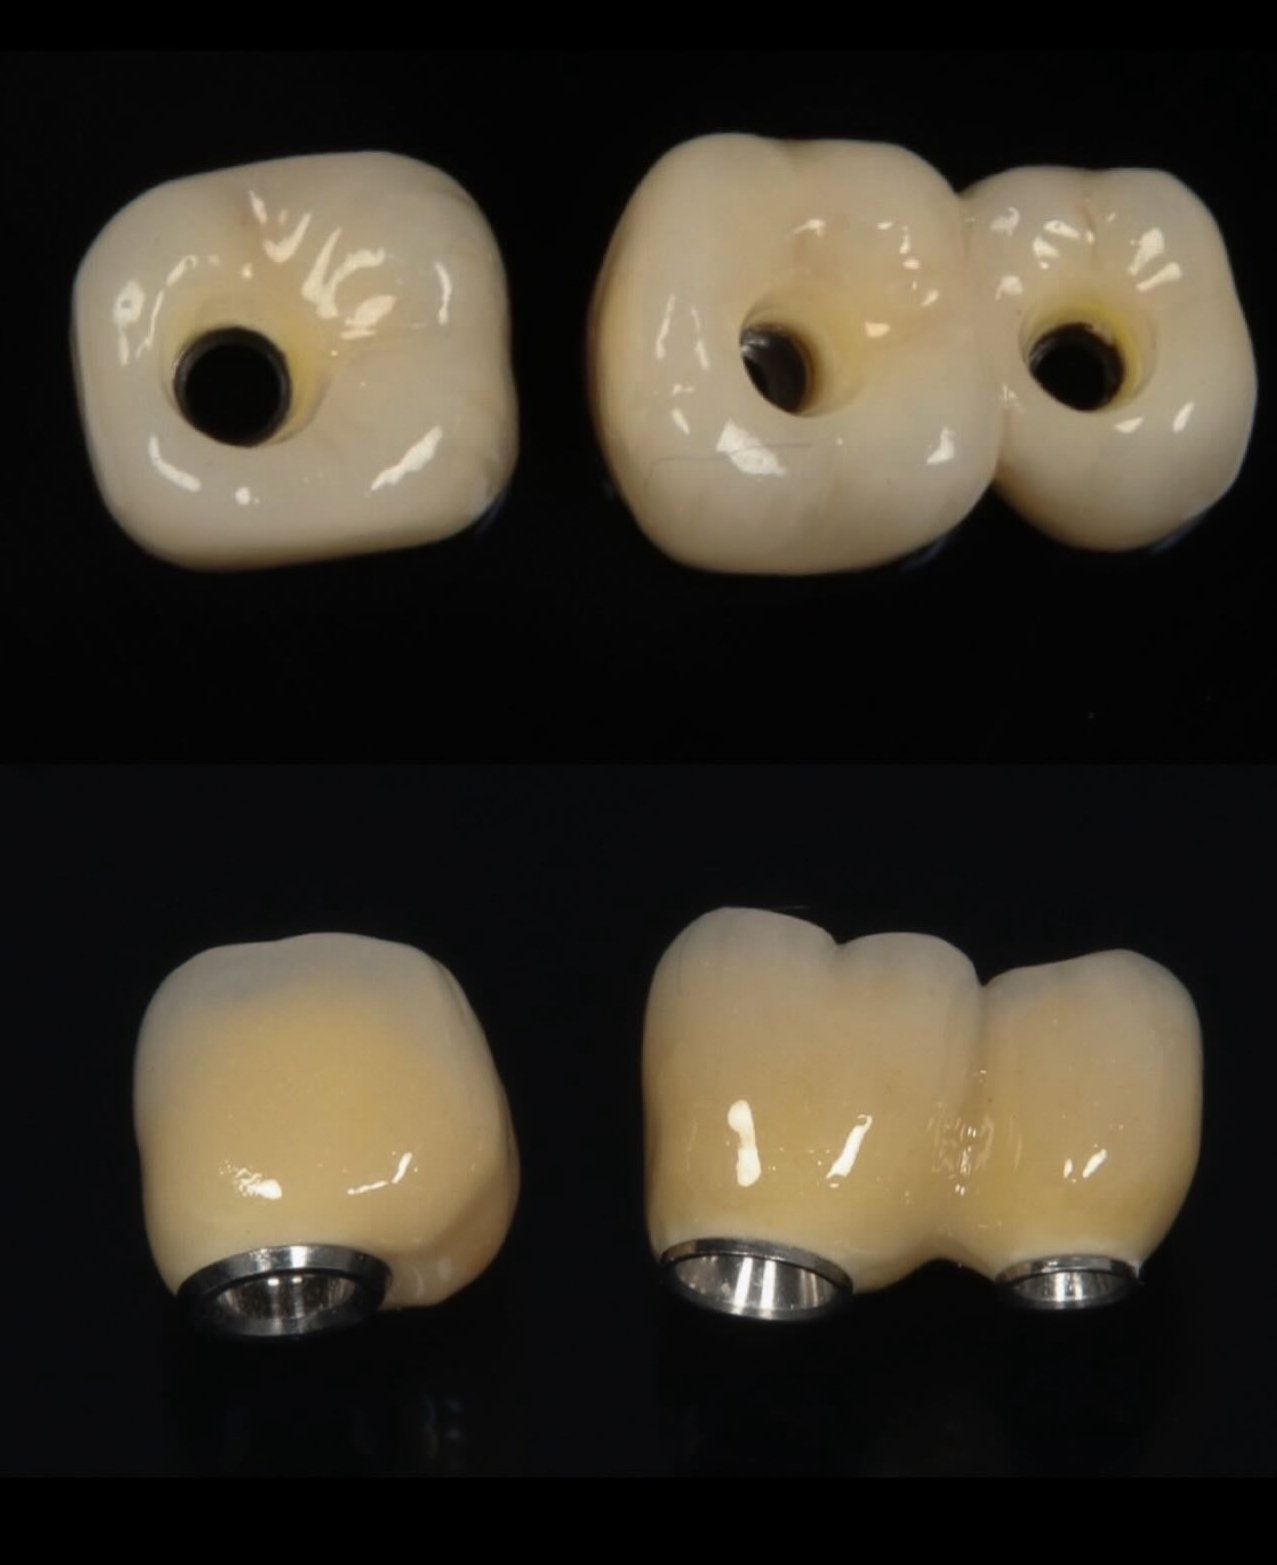

4. Rehabilitación: instalación de corona, puente o prótesis fija.

Galería de casos

Algunos resultados obtenidos en nuestra clínica.

Caso implantes 1 Caso implantes 2 Caso implantes 3 Caso implantes 4 Caso implantes 5 Caso implantes 6 Prótesis sobre implantes - Caso 7 Prótesis sobre implantes - Caso 8 Prótesis sobre implantes - Caso 9

Sí, los implantes se ven completamente naturales. Las coronas se diseñan para que coincidan perfectamente con el color, forma y tamaño de tus dientes naturales.